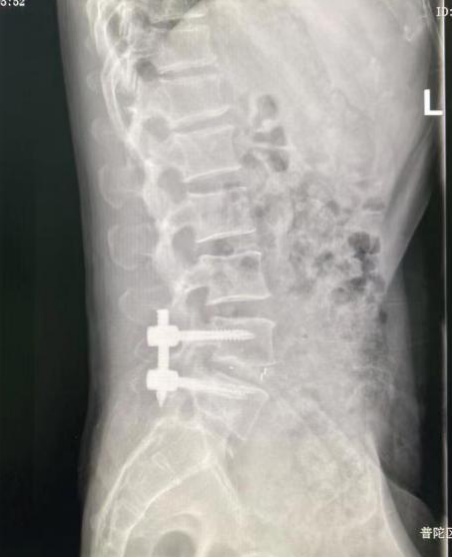

术后复查,内固定位置良好